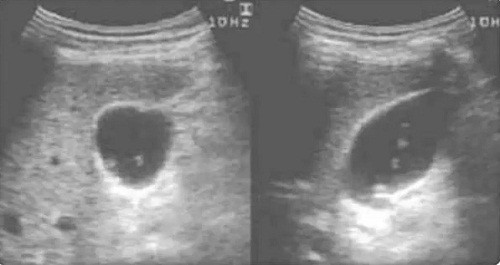

Quá trình kiểm tra, bác sĩ nhận thấy gan trái bệnh nhân gần như bị “đục rỗng”, gan ứ mủ sưng như trái bóng nên yêu cầu nhập viện gấp. Tại đây, bác sĩ tiến hành chọc thủng túi mủ, cắt bỏ nửa gan trái. Thông qua mẫu phẩm thu được, bác sĩ ngỡ ngàng phát hiện cấu trúc giống khối u trong gan hóa ra là một khối viêm, thậm chí có kí sinh trùng bên trong.

Hình ảnh chụp gan ứ mủ của bệnh nhân.